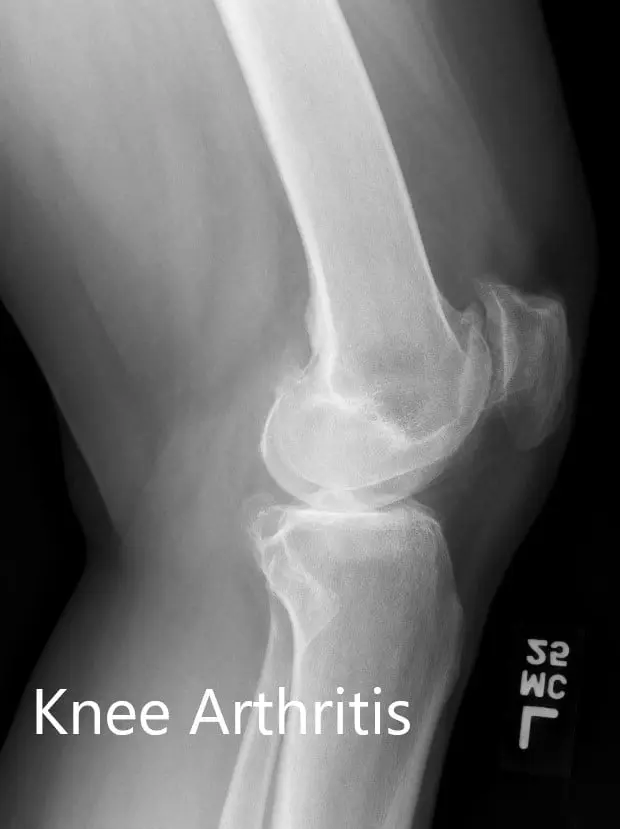

Preoperative X-ray of the left knee showing AP and lateral views

Preoperative X-ray of the left knee showing AP and lateral views - img 2